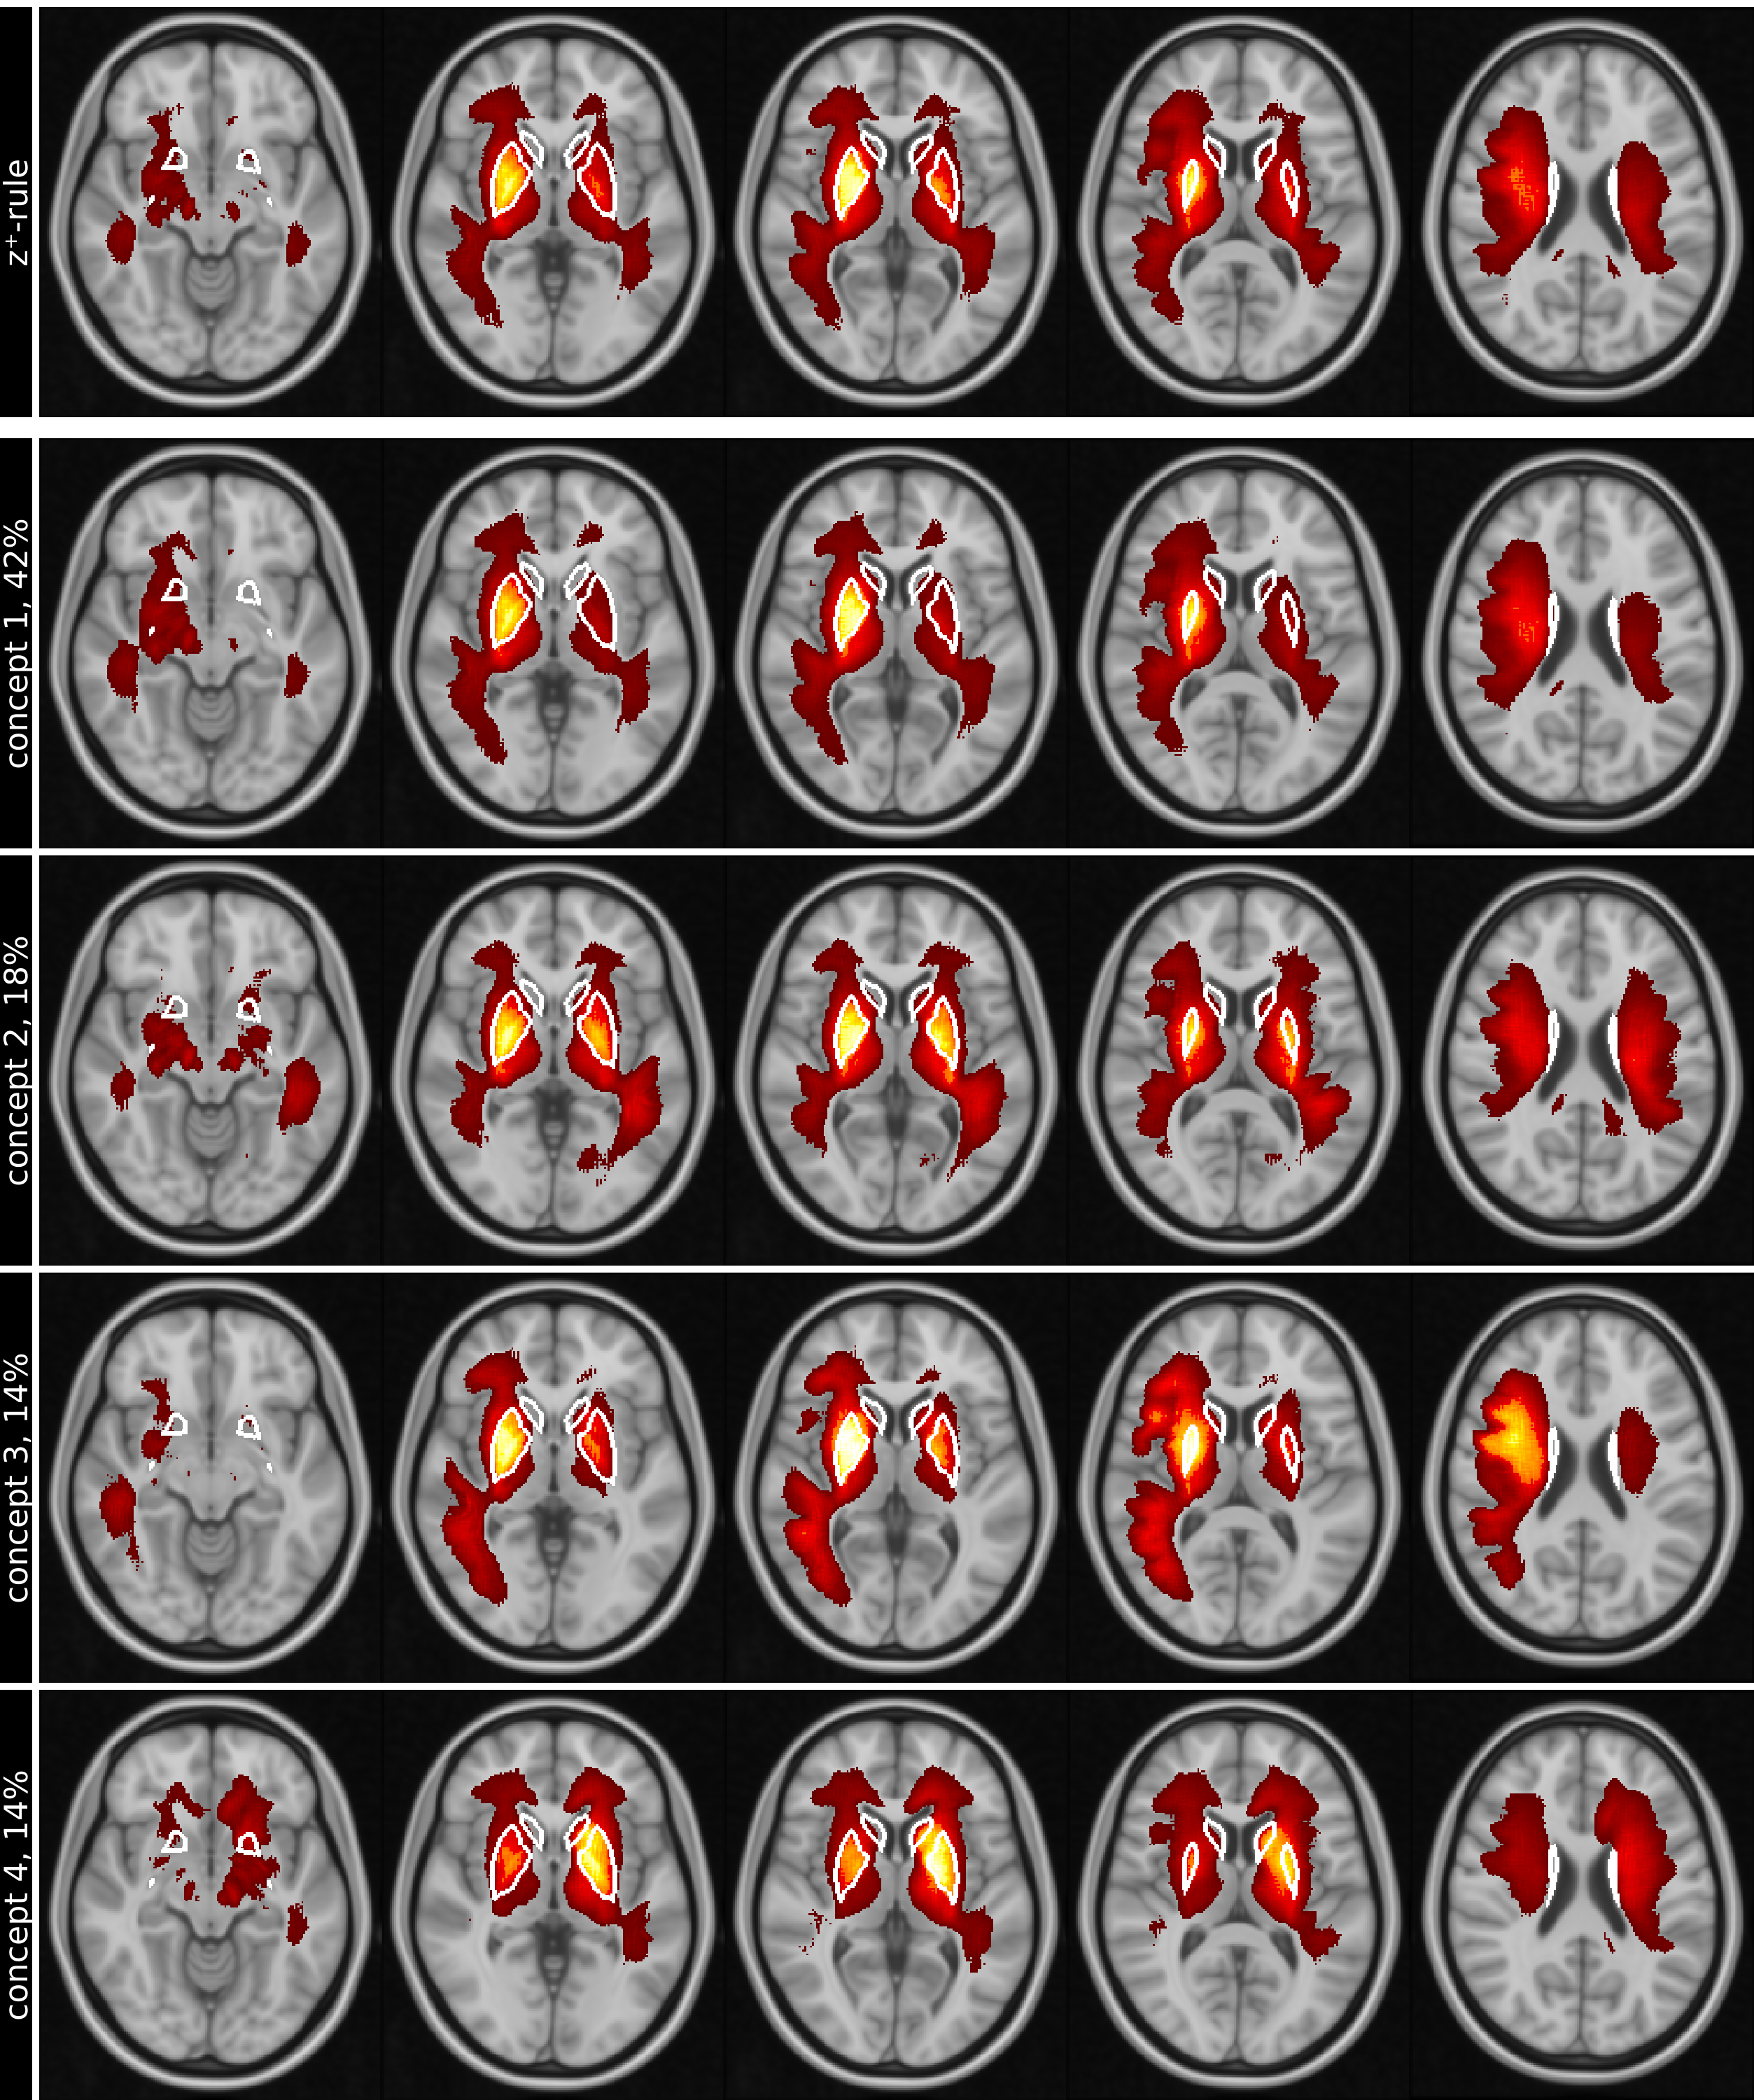

Figure  3 shows the five top ranked test images for each concept on the same transversal slice, while figures 4 and 5 show the mean concept maps for NC and AD on five transversal slices.

Refer to caption

Figure 4: Row (1) shows the conventional mean global heat maps created for NC using LRP-z+superscript𝑧z^{+}-rule for 5 slices (columns), overlaid on the MNI152 standard-brain 1mm template. In comparison, rows (2) to (5) show the 4 most important concepts on the same slices, ranked by their relative importance (percentage next to name) for the classification results. Positive relevance, shown as red-yellow, highlight regions in concepts with higher attributions. White lines in slices outline the basal ganglia. Images are shown in standard-radiological view, causing the left and right side of the brain to be flipped.